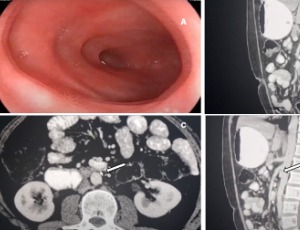

Polycystic liver in autosomal dominant polycystic kidney disease

A 61-year-old man presented for routine health checkup. The patient was asymptomatic. His medical history was autosomal dominant polycystic kidney disease (ADPKD). Laboratory results and urinalysis were unremarkable. Abdominal computed tomography showed innumerable hepatic cysts of different sizes and diffuse small renal cysts (Figures 1A-1C). Polycystic

J Clin Exp Gastroenterol, 2025, Volume Volume 4, Issue Issue 1, p15-16 | DOI: 10.46439/gastro.4.025